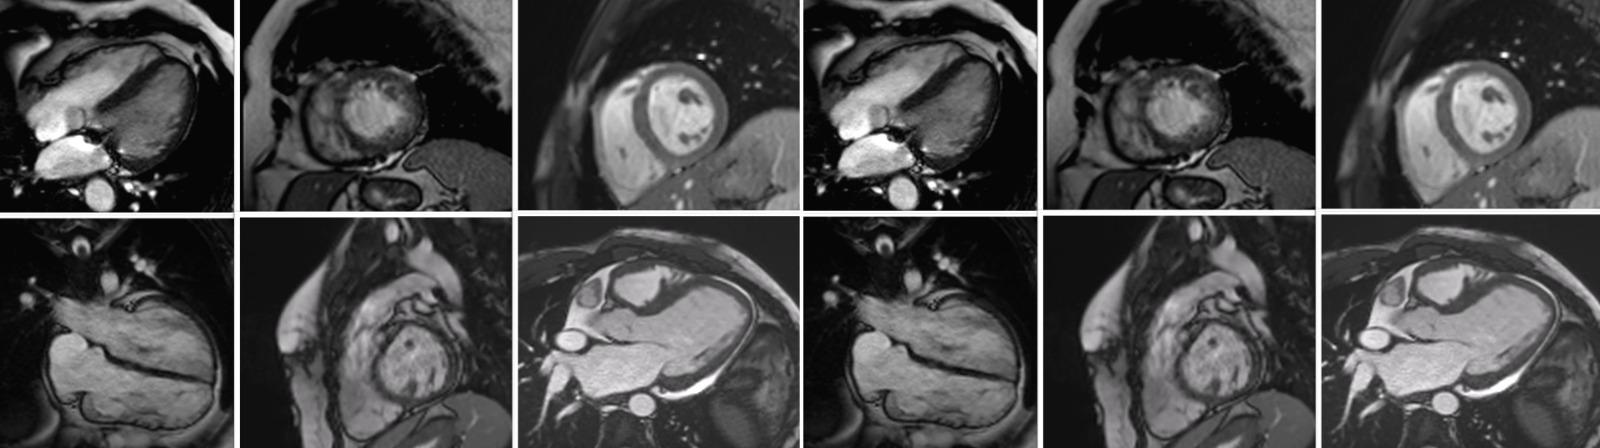

Rezonanța magnetică cardiovasculară (Cardio-RM) este cea mai avansată metodă imagistică de evaluare a funcției inimii. La Emerald, investigația este realizată de o echipă formată dintr-un medic radiolog cu experiență și un medic cardiolog specializat în RM cardiovasculară, în timpul acesteia fiind preluate peste 1500 de imagini de pe inimă, cu ajutorul unui aparat de ultimă generație, mai rapid, mai precis și mai silențios. Rezonanţa magnetică este o scanare nedureroasă și inofensivă, ce permite să privim în interiorul corpului fără utilizarea razelor X. Cu ajutorul unui magnet şi a undelor radio obţinem imagini detaliate, de foarte bună calitate cu privire la structura şi funcţia inimii.

Este indicată în cazul următoarelor patologii: Insuficiență cardiacă, Cardiomiopatie hipertrofică, Miocardită, Fibroză miocardică, Cardiomiopatie dilatativă, Displazie aritmogenă de ventricul drept, Bloc de ramură stângă, Extrasistole ventriculare, Aritmii ventriculare, Resincronizare cardiacă, CRT, Talasemie, Hemocromatoză, Amiloidoză, Boala Fabry, Regurgitare aortică, Insuficiență aortică. La Emerald se efectuează și rezonanță magnetică cardiacă de stres, o investigație nouă în Romania, dar foarte utilizată în celelalte țări europene, dedicată unor patologii speciale, cum ar fi: Boală cardiacă ischemică, Infarct miocardic acut, Cardiopatie ischemică, Angină pectorală, Stenturi coronariene, Bypass aorto-coronarian.